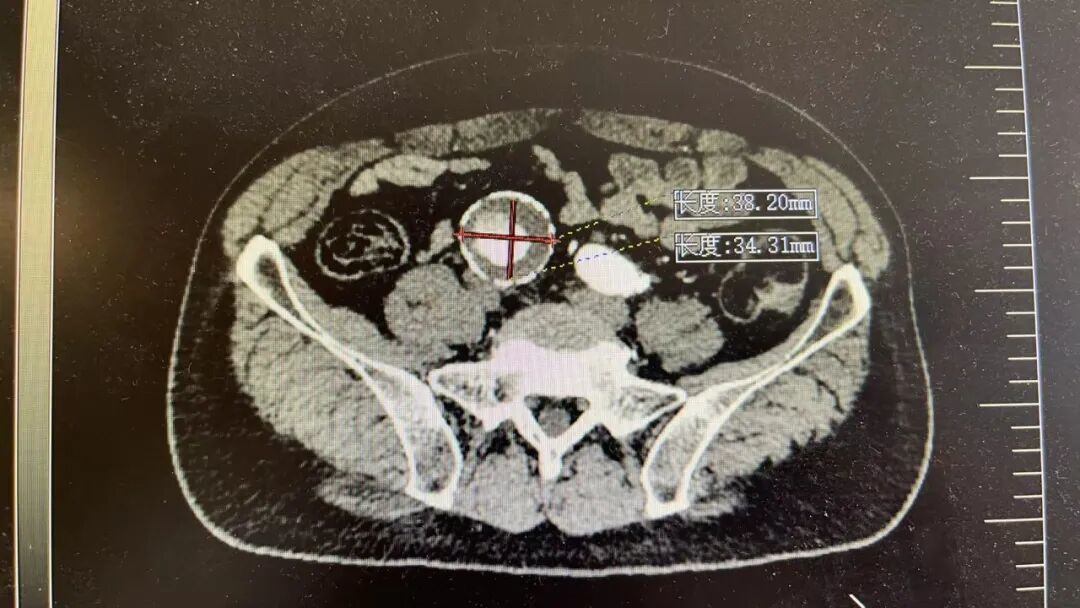

这两位患者情况差不多,他们平日里身体并无明显不适,在一次常规体检中,腹部超声检查结果显示,腹主动脉存在瘤样扩张,进一步检查确诊为腹主动脉瘤,并同时累及双侧髂总动脉,形成髂动脉瘤。

腹主动脉是人体腹部最粗大的一根动脉,大致位于肚脐的后面、脊柱的前面,负责将心脏泵出的血液输送到下半身。到了肚脐下方约三四指的位置,它分叉成左右两条髂总动脉,继续向双腿延伸。患者情况比较特殊,动脉瘤不仅累及了腹主动脉主干,还向下延伸到了分叉区域。

这颗炸弹,需要尽快拆除。但手术的最大难点,不仅在于如何封堵动脉瘤,更在于如何保住一条重要的血管髂内动脉。

北京大学人民医院皇冠篮球比分网_澳门现金网-球探体育:医院血管外科团队用一个通俗的比喻解释了其中关键:腹主动脉分叉后形成的左右两条髂总动脉,每条又分出一条髂内动脉。这条髂内动脉虽然不算粗,却承担着为臀部肌肉、盆腔器官以及会阴部供血的重任。

手术最大的挑战,是如何在隔绝动脉瘤的同时,精准重建髂内动脉。采用腹主动脉分支支架、髂动脉分支支架技术重建腹主动脉、髂总动脉、髂外动脉、髂内动脉,是目前公认的既能隔绝动脉瘤、又能最大限度保留盆腔功能的最优解之一。这项技术操作复杂,对医生的技术和团队的配合要求极高,经过手术团队精细操作,手术顺利结束,患者已顺利出院。